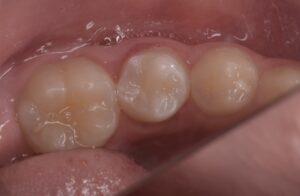

当日根管治療を実施し、根管充填まで行なった

翌日、痛みがないことを確認し、ダイレクトボンディングで治療を終了とした